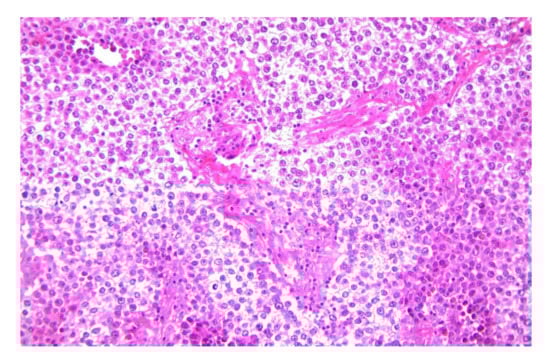

2.3. Yolk Sac Tumor (Endodermal Sinus Tumor)

2.3.2. Microscopic Features